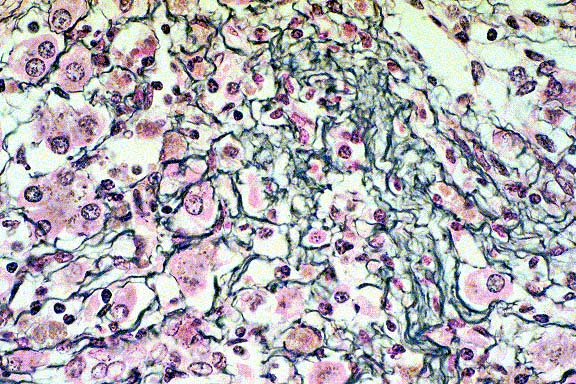

10x

obj

- Case14-3. Liver. There is diffuse dissociation of

hepatocytes, increased numbers of cells in the sinusioids, and

pale eosinophilic material (collagen) in centrilobular locations.

Central veins are inconspicuous. Kupffer cells contain abundant

pigment.

obj, Reticulin stain

- Case14-3. Liver. Reticulin stain demonstrates increased

sinusoidal reticulin extending from portal to centrilobular areas

of the liver.

40x

- Case14-3. Liver. This magnification shows abundant

reticulin and individualization of hepatocytes.

obj, Trichrome stain

- Case14-3. Liver. Blue staining areas localize collagen.